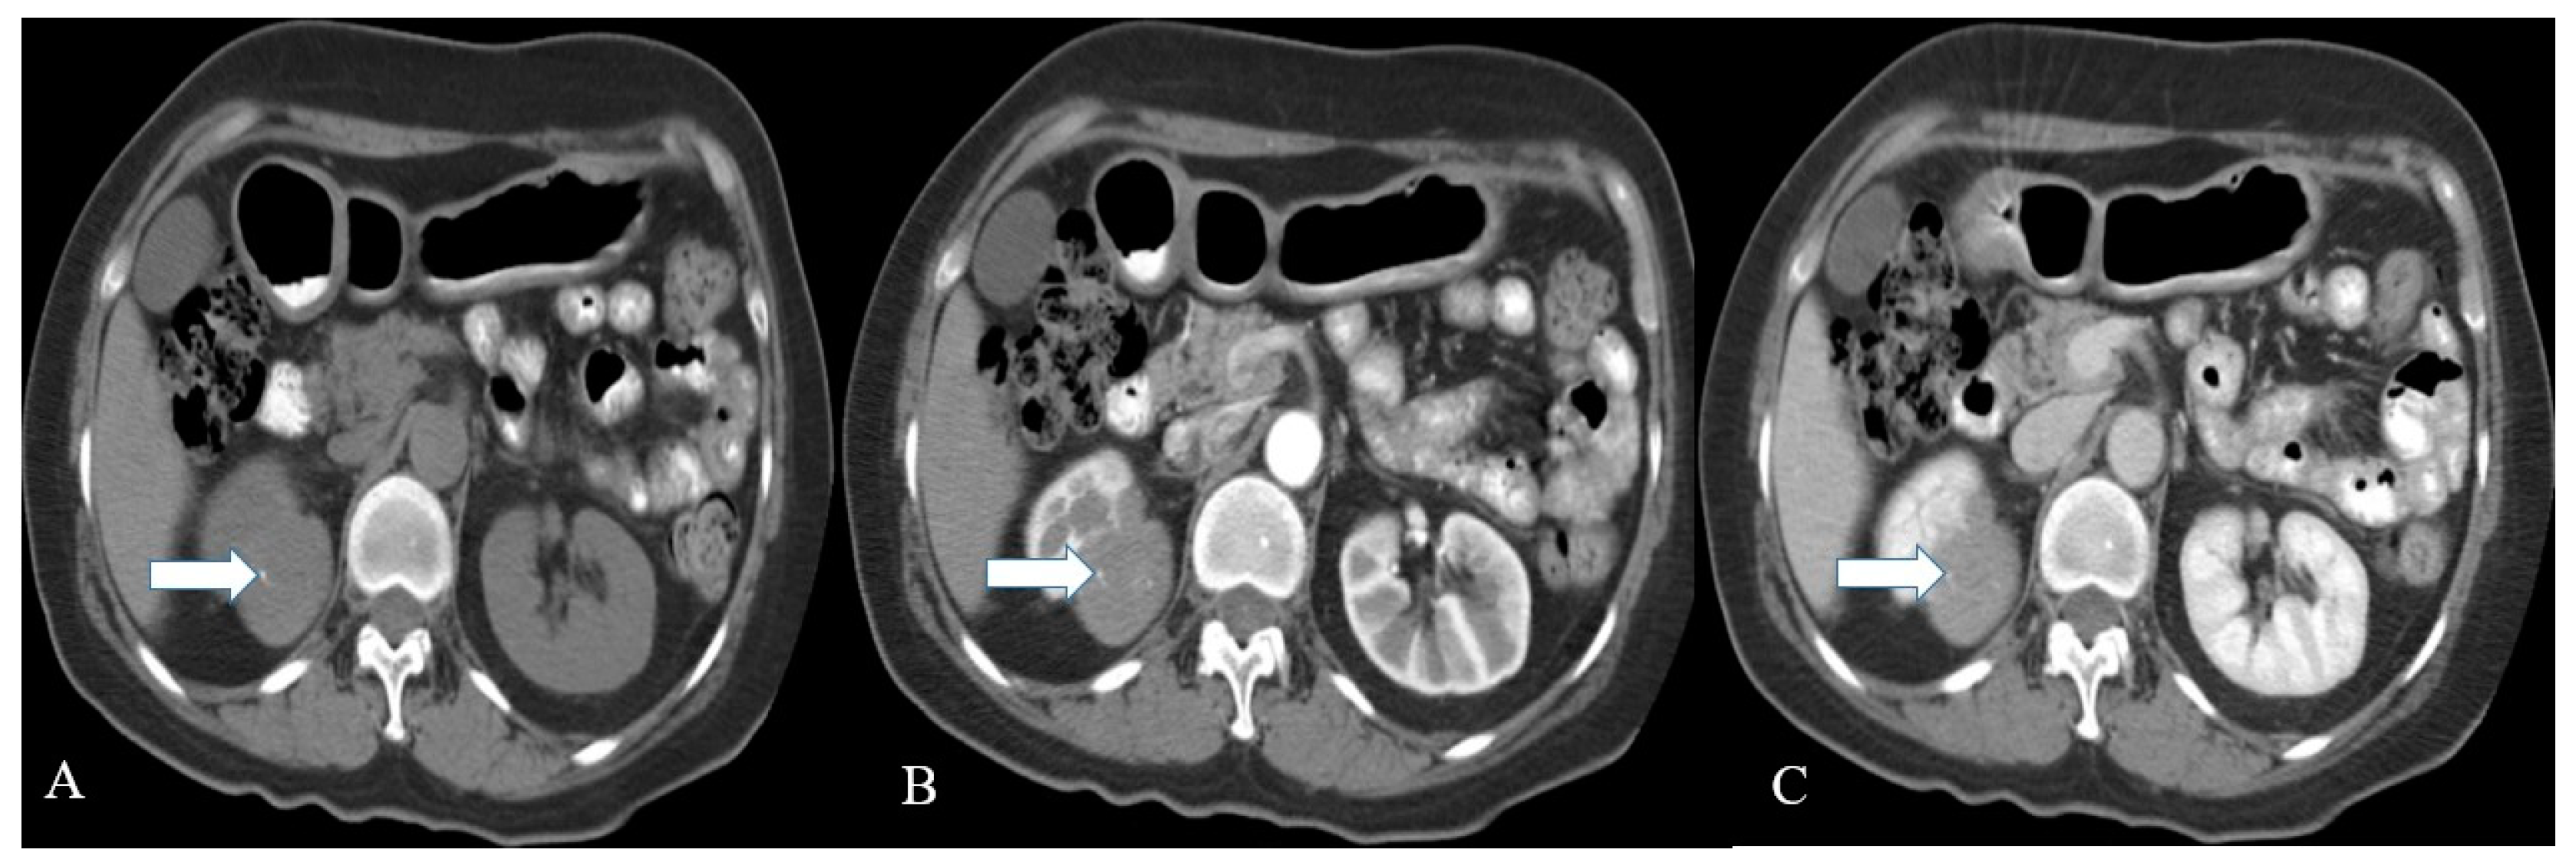

2.3. Imaging

| Renal NET | Heterogeneous solid tumor with cystic component as well; Minimal enhancement on contrast administration; Octreotide scintigraphy: High affinity for somatostatin in 87% of patients. | Heterogeneous signal intensity on T1 and T2WI with areas of high signal intensity on T1WI due to hemorrhage; The mass enhances with contrast administration |